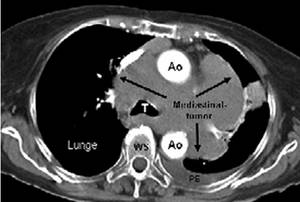

Im Röntgen des Brustkorbes kann die Verbreiterung oder Verlagerung des Mediastinums erkannt werden. Zur weiteren Abklärung ist eine Computertomographie (CT) (Abb.2), evtl. ergänzt durch eine Magnetresonanz-tomographie (MRT) oder eine Angiographie (Blutgefäßdarstellung), erforderlich. Zur genauen Diagnosestellung ist meist eine feingewebliche Untersuchung von Gewebsproben durch eine Punktion von außen oder über eine Bronchoskopie oder Ösophagoskopie notwendig.

Abb2: Computertomogramm (CT) eines) Patienten mit großem Mediastinaltumor

LK = Lymphknoten, T = Trachea, AO = Aorta, WS = Wirbelsäule, BZ = Biopsiezange, VM = vorderes Mediastinum, PE = Pleuraerguß